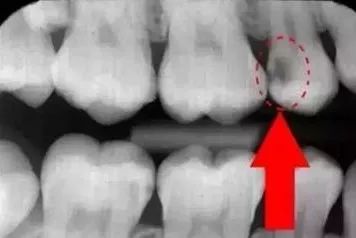

口腔全景片怎么看有没有蛀牙?

一般来说,常见的蛀牙通常可以通过牙片发现,尤其是龋坏比较多(如下图),在牙片上会出现黑色阴影的缺损。

因此,正是因为牙片拍摄及时,医生给予了正确的判断,在蛀牙初期便提前治疗,避免了越发严重的后果。

画圈圈的部分就说明牙齿已经在慢慢的龋齿化,慢慢的蛀坏!

曲面断层片怎么看科普知识:你会看牙片嘛?今天手把手教你看!_https://www.jmylbn.com_新闻资讯_第13张

暗的部位说明龋齿已经非常严重了!

下面这个是接近牙髓了。